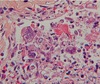

- inflammation in appendicitis

- way too many cells throughout

- epithelial surface being destroyed